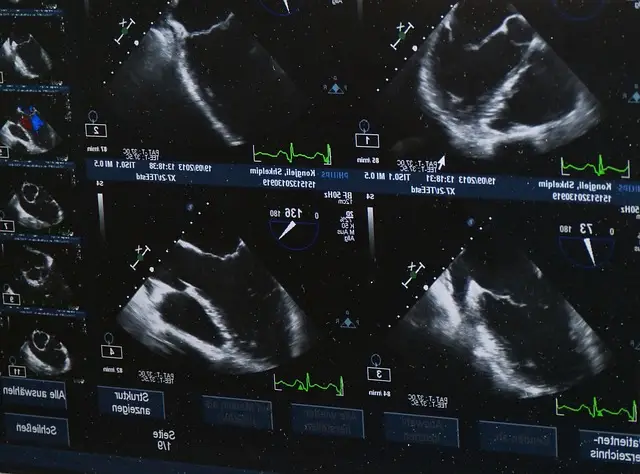

초기 증상은 다른 건강 문제와 혼동될 수 있어 정기적인 자가 검진과 마모그래피 검사가 중요하며, 조기 발견에 큰 도움을 줄 수 있습니다. 이는 유방암을 조기에 발견하여 치료 결과를 개선하는 데 중요한 역할을 합니다.